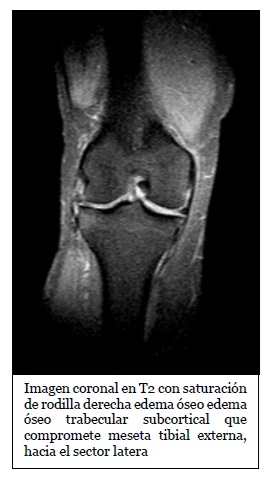

Imagen coronal de secuencia potenciada en T2 con saturación grasa de la rodilla derecha en paciente con lesión por traumatismo en valgo. Edema óseo en la

Fuente: https://epos.myesr.org/posterimage/esr/seram2014/124014/mediagallery/577012